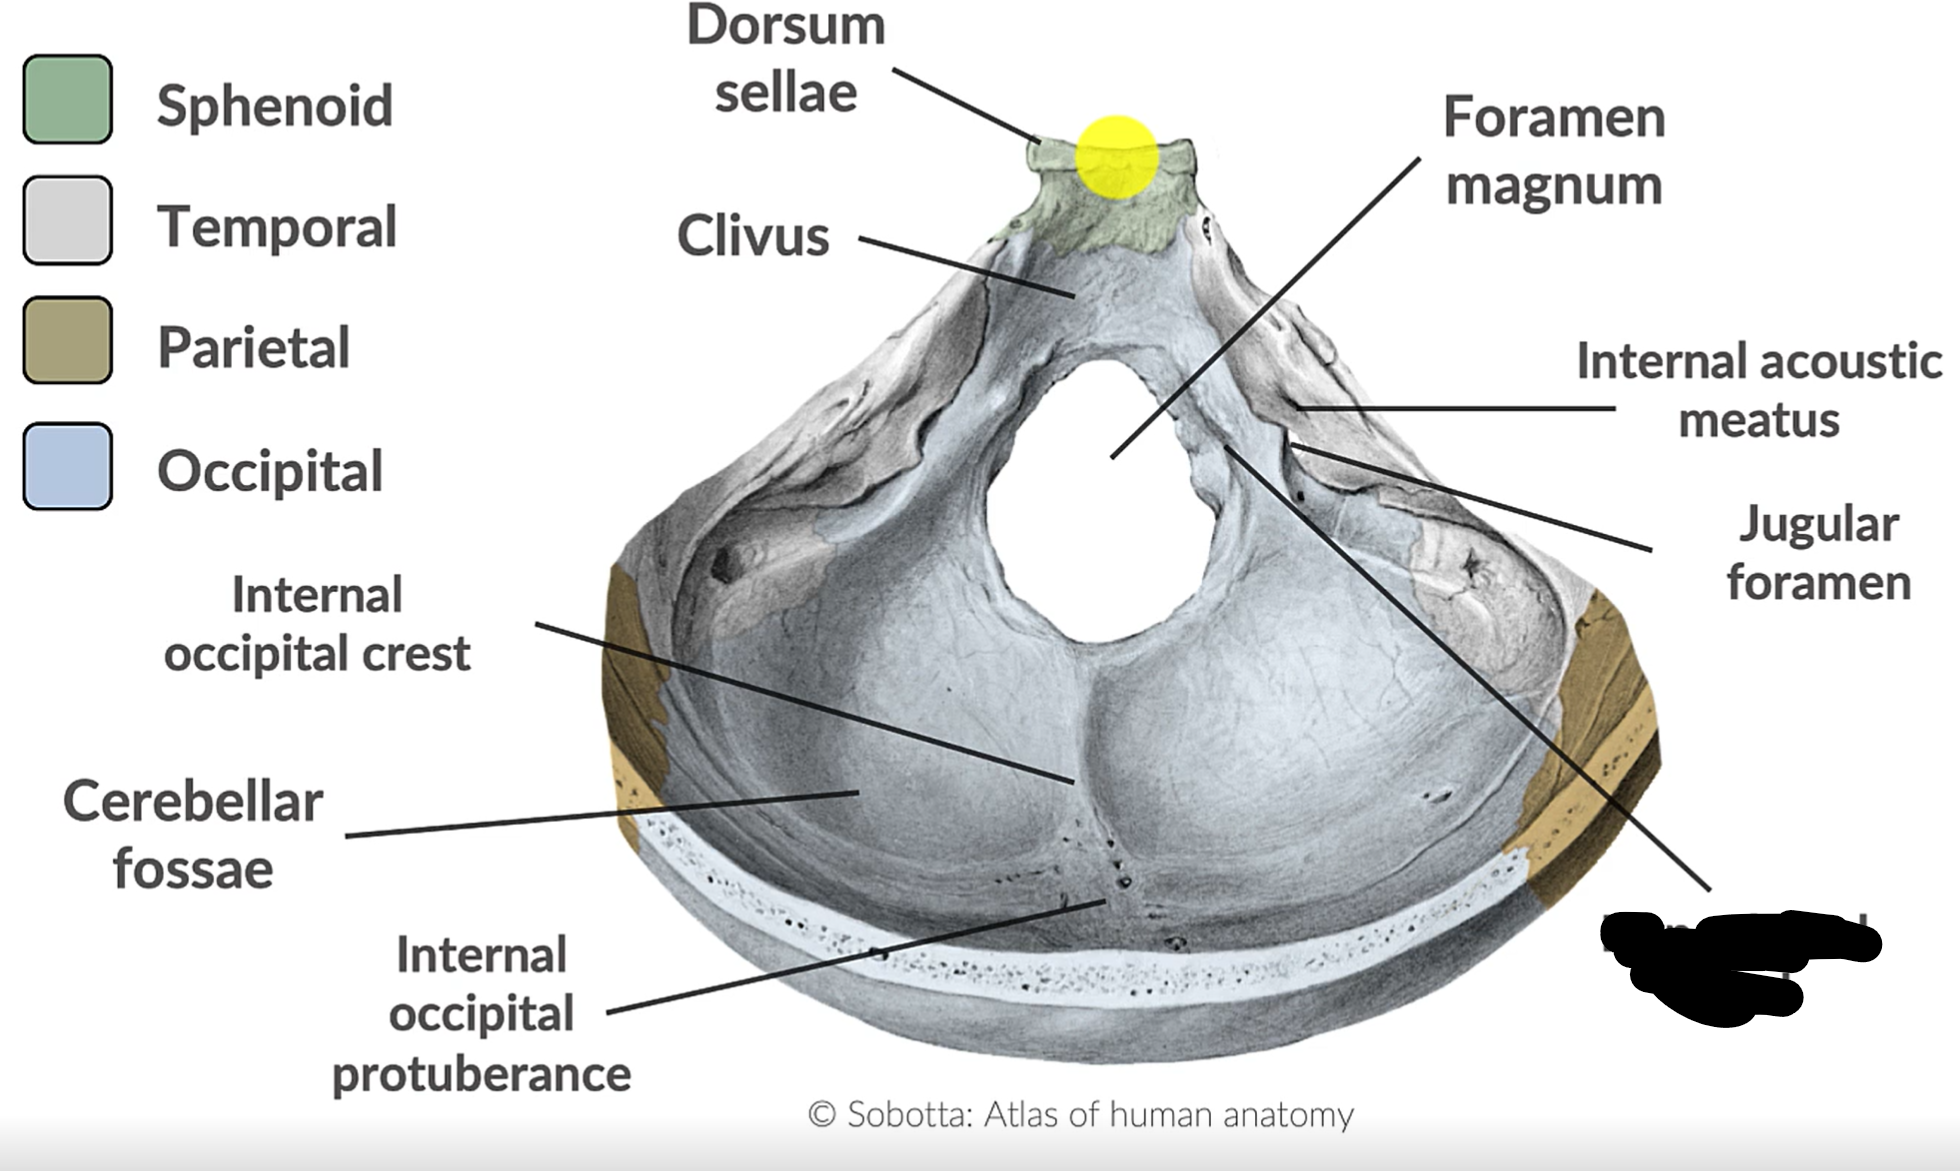

What forms the posterior cranial fossa?

Occipital, temporal, parietal and sphenoid bones

Foramen magnum

Jugular foramen

Internal acoustic mediatus

Hypoglossal canal